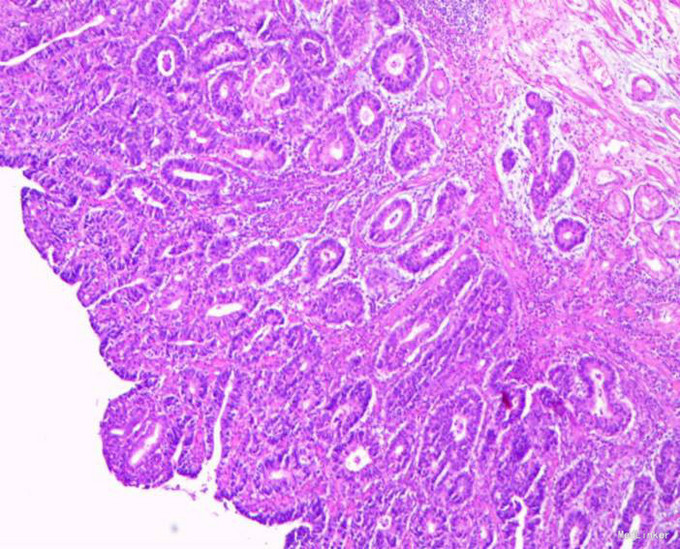

随访:出院后2周,电话随访患者,一般情况良好,无不适主诉。 讨论:该患者胃镜见一胃窦前壁粘膜隆起,表面粘膜粗糙,病理示:慢性萎缩性胃炎,伴部分腺体中重度不典型增生,局灶重度不典型增生,超声胃镜病灶未突破粘膜下层,有胃ESD手术指征,故行全麻下胃ESD术。术后病理:胃窦前壁肿瘤:腺上皮高级别上皮同瘤,部分癌变,病变大小1.5*1.1*0.3cm,基底及切缘未见癌。说明手术成功,切缘及基底均无肿瘤侵及。对于早癌患者我们完全可以通过采用ESD方法治愈患者,胃镜下切除早癌较腹腔镜创伤更小。我和患者解释时是这样说的:腹腔镜是微创,而我们内镜下ESD则是微微创。